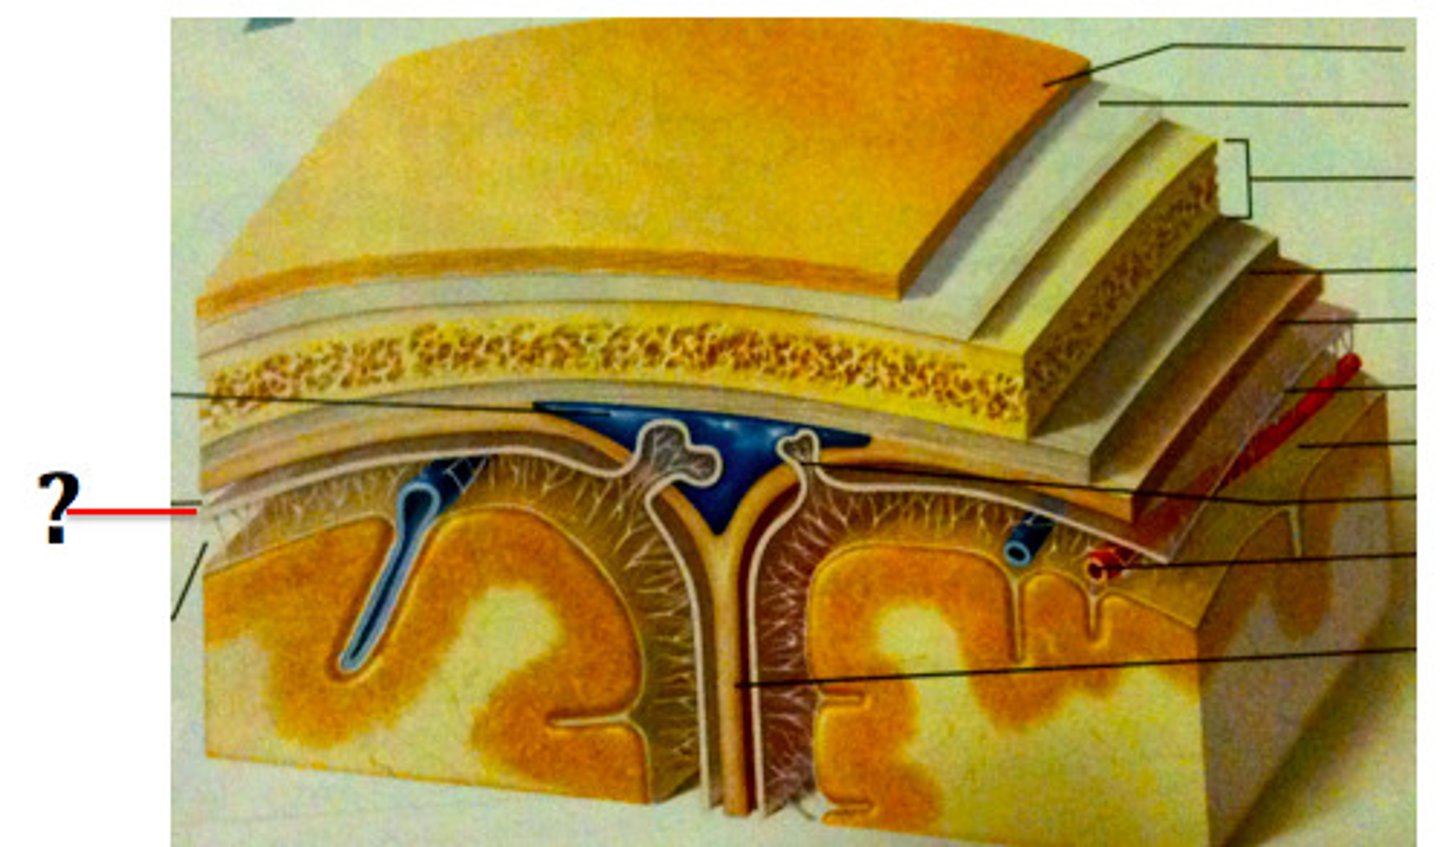

3 layers make up the meninges

dura mater, arachnoid mater, pia mater

dura mater

outer periosteal layer & inner meninges layer

periosteal and meningeal

arachnoid

middle layer of meninges; weblike appearance that attaches it to deepest layer

arachnoid trabeculae

subdural space

space between dura mater and arachnoid mater

subarachnoid space

arachnoid mater

pia mater

the delicate innermost membrane enveloping the brain and spinal cord.